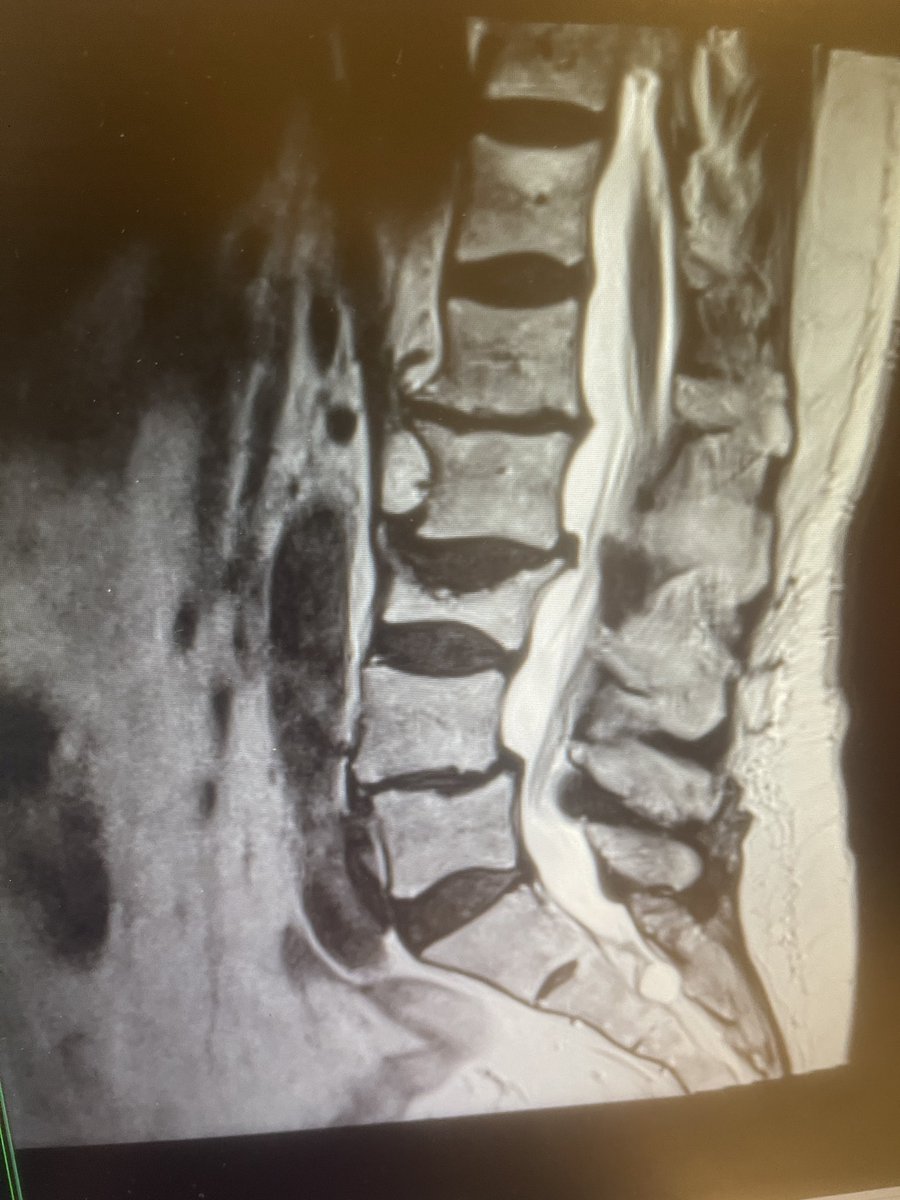

Case I performed recently.